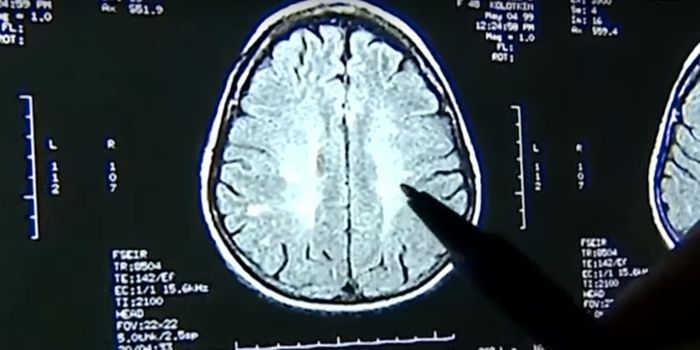

OCT 12, 2021Clinical & Molecular DXScientists have discovered a novel biomarker in the blood that acts as an early warning sign for dementia: microRNA. The ...

OCT 11, 2021Genetics & GenomicsWhile amyloid plaques are a hallmark of Alzheimer's disease, the neurological disorder has also been linked to inflammat ...

DEC 10, 2020Genetics & GenomicsIt's thought that by the year 2060, there will be 14 million Americans living with Alzheimer's disease.